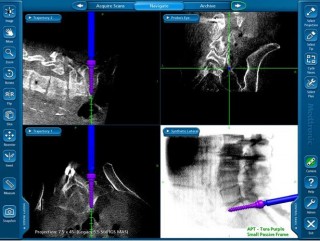

Il sistema O-Arm fornisce una soluzione completa e di facile utilizzo per le procedure strumentate di chirurgia vertebrale, offrendo imaging intraoperatorio multi-dimensionale di elevata qualità, la possibilità di acquisire immagini fluoroscopiche 2-D e 3-D e visioni multi-piano che consentono di migliorare il processo clinico-decisionale

Il sistema O-Arm è caratterizzato da un tubo radiogeno (gantry) che, in fase intra-operatoria, circonda il corpo del paziente ed è libero di ruotarvi attorno a 360°, acquisendo immagini fluoroscopiche 2-D (movimento dei raggi X in tempo reale) ed immagini TC 3-D.

Il sistema di neuronavigazione StealthStation, già in dotazione presso la Unità Operativa di neurochirurgia, è il più avanzato sistema di navigazione attualmente disponibile, in grado di integrare automaticamente le immagini intra-operatorie acquisite da O-arm.

La piattaforma O-arm / STealthStation fornisce dunque un sicuro supporto ed una guida per il chirurgo durante la procedura, minimizzando il rischio di lesione alle strutture nervose.